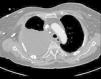

We report the case of an 84-year-old woman, with a history of arterial hypertension, type 2 diabetes, diabetic nephropathy treated with dialysis via a right jugular vein catheter (thrombosed 3 months before admission), and spinal stenosis (L4–L5). She was referred to the emergency department when she reported cough during a hemodialysis session, and pulmonary auscultation revealed diminished breath sounds in the lower half of the right hemithorax. She did not have fever or dyspnea. In the days before admission, she had received amoxicillin/clavulanate for a possible urinary infection. Physical examination showed arteriovenous fistula for hemodialysis access in the left forearm, rhythmic heart sounds with a grade III/IV systolic murmur in the mitral valve, and diminished breath sounds in the right lung base. Complete blood count and biochemistry results were normal, except for proBNP 1750 and triglycerides 99mm/dl. Chest radiography revealed pleural effusion in the lower third of the right hemithorax, thickening of the minor fissure, and catheter in the right jugular vein. A diagnostic thoracocentesis was performed, obtaining milky fluid with pH 7.30, ADA 21U/l, LDH 119U/l, glucose 214mg/dl, total proteins 4.1g/dl, cholesterol 94mg/dl, and triglycerides 870mg/dl. Cytology was negative for malignancy. Chest CT findings included large right pleural effusion, passive atelectasis of the right lung with mediastinal shift, large collateral circulation in the right hemithorax through the azygos/hemiazygos system, and superior vena cava stenosis with a right jugular vein catheter (Fig. 1). The central jugular catheter was removed under fluoroscopic control, and replaced by a femoral catheter. Before chylothorax was diagnosed, a pleural drain was placed, which collected 1800ml. Chest radiograph on discharge showed complete resolution of the pleural effusion, which did not relapse during follow-up.